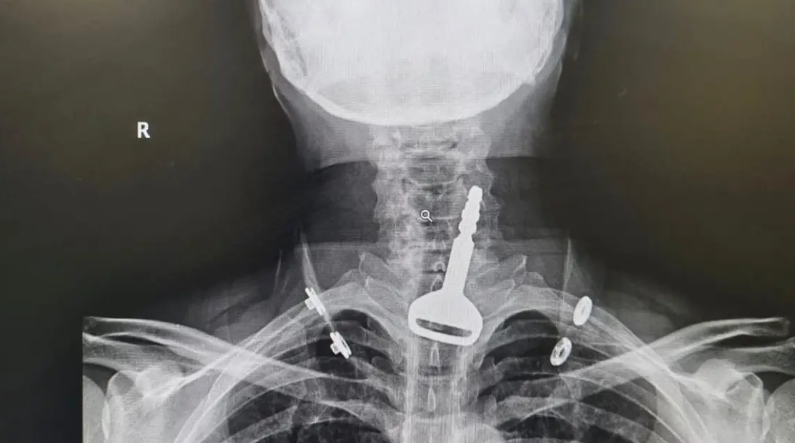

أربعيني سعودي يبتلع مفتاح سيارته

تمكن فريق طبي بمدينة القنفذة السعودية من استخراج مفتاح سيارة عالق بالجهاز التنفسي لمريض أربعيني، في عملية استغرقت 15 دقيقة…